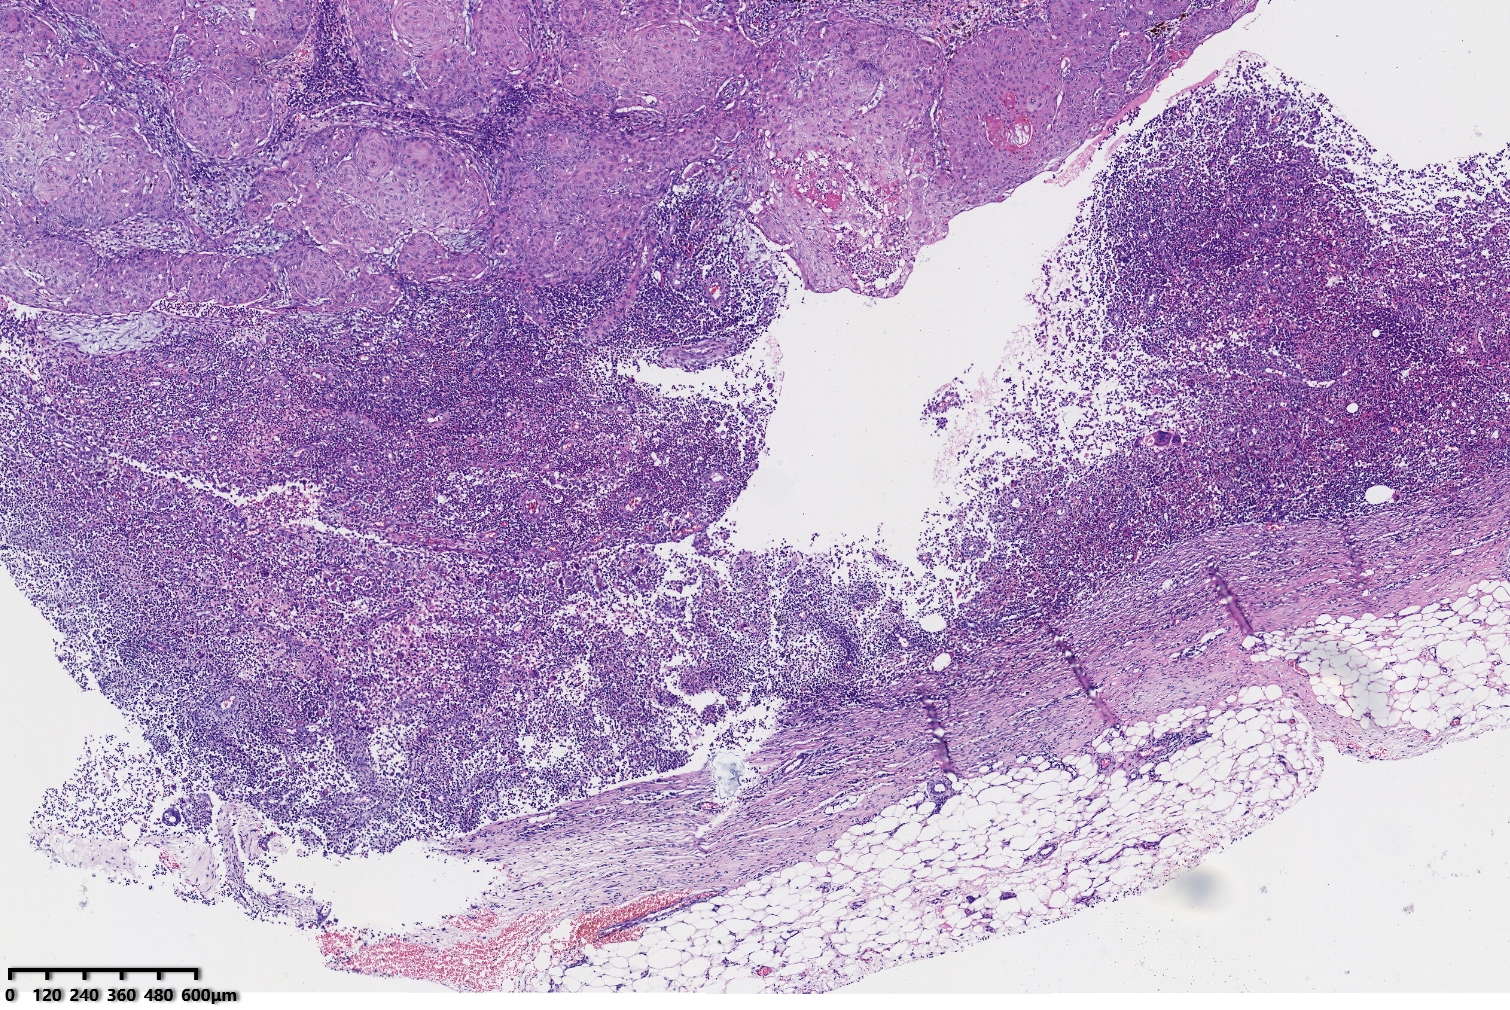

倒置型毛囊角化?

性别

男

年龄

49岁

临床诊断

一般病史

右腋下包块

标本名称

大体所见

考虑增生性外毛根鞘瘤?